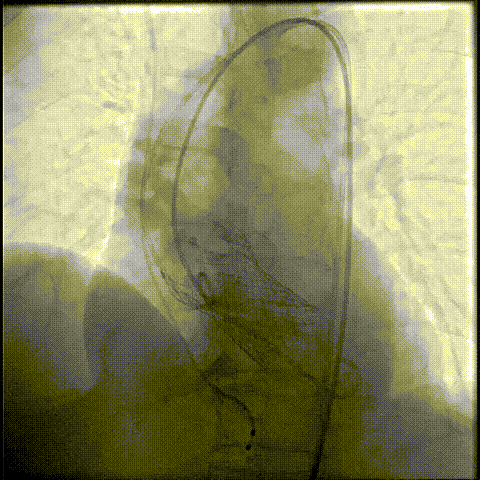

主动脉根部造影